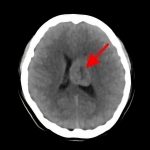

断層撮影

手術前1

手術前2